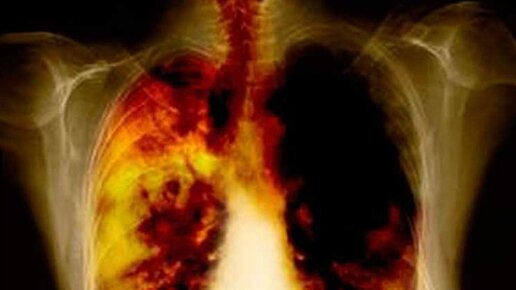

Гнойный плеврит легких

Одним из коварных и опасных заболеваний является гнойный плеврит, который выявляют у людей любого возраста, пола и расовой принадлежности. Пиоторакс (его второе название) – это заболевание, характеризующееся воспалением плевры с образованием гнойных масс в плевральной полости. При отсутствии своевременно медицинского вмешательства возможно наступление летального исхода. Причины возникновения Пиоторакс — самостоятельное заболевание, скорее осложнение, так как является результатом других патологий, уже прогрессирующих в организме...